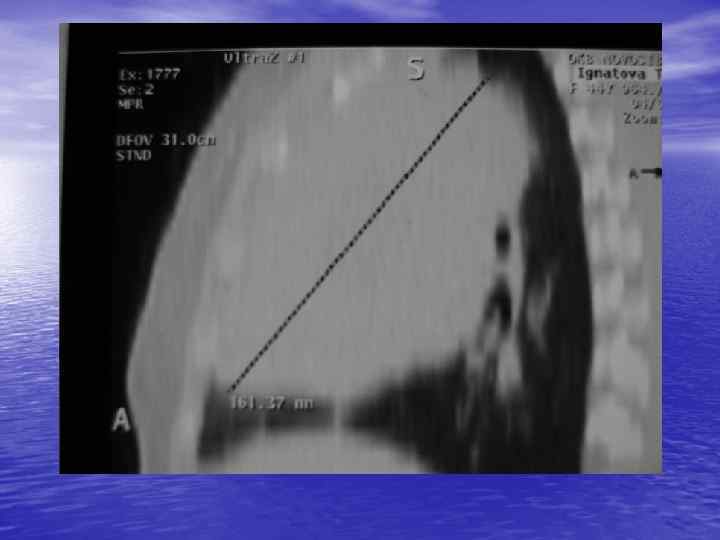

Структурный анализ Оценка основных макроскопических признаков: - положение - форма - размеры - характер контуров и структур патологически измененных участков

Структурный анализ